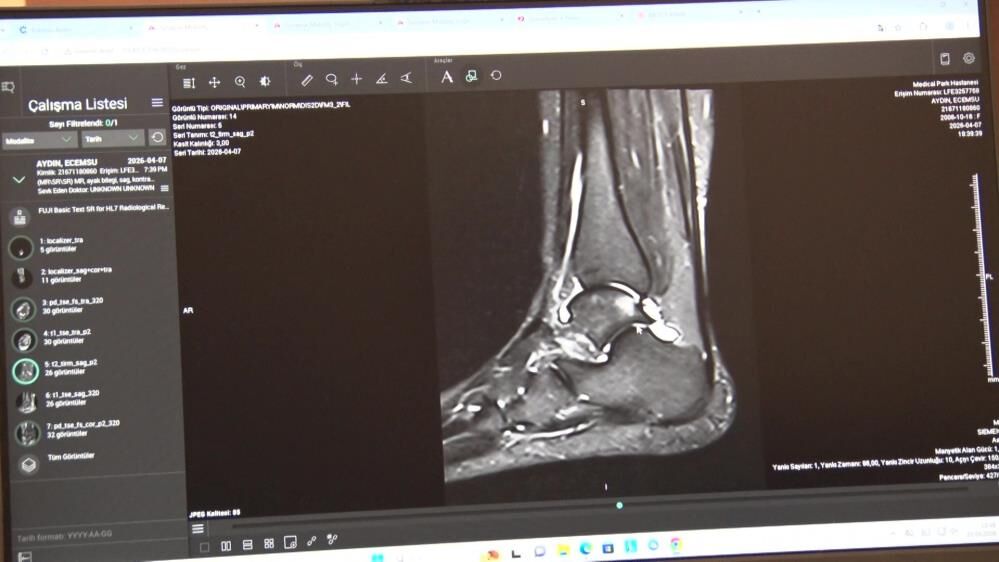

En sık görülen yaralanmalar diz ve tendonlarda

Klinik pratikte en sık karşılaştıkları spor yaralanmalarına da değinen Serarslan, özellikle halı sahada yapılan futbolun sakatlık riskini artırdığını belirterek, 'Bizim klinik pratiğimizde en sık karşılaştığımız sakatlıkları birkaç gruba ayırabiliriz. Birincisi ani travmayla gelişen akut yaralanmalar, ikincisi ise zamanla tekrarlayan zorlanmalara bağlı oluşan kronik problemler. En çok karşılaştığımız akut travmalar arasında diz yaralanmaları, ön çapraz bağ yaralanmaları, menisküs yaralanmaları, kas travmaları, kas yırtıkları, omuz çıkıkları, omuz bağ ve kas yırtıkları ile özellikle aşil tendon yaralanmaları yer alıyor. Türkiye'de halı sahada futbol çok yaygın ama bu zemin sakatlık açısından da çok riskli bir alan oluşturuyor' ifadelerini kullandı.